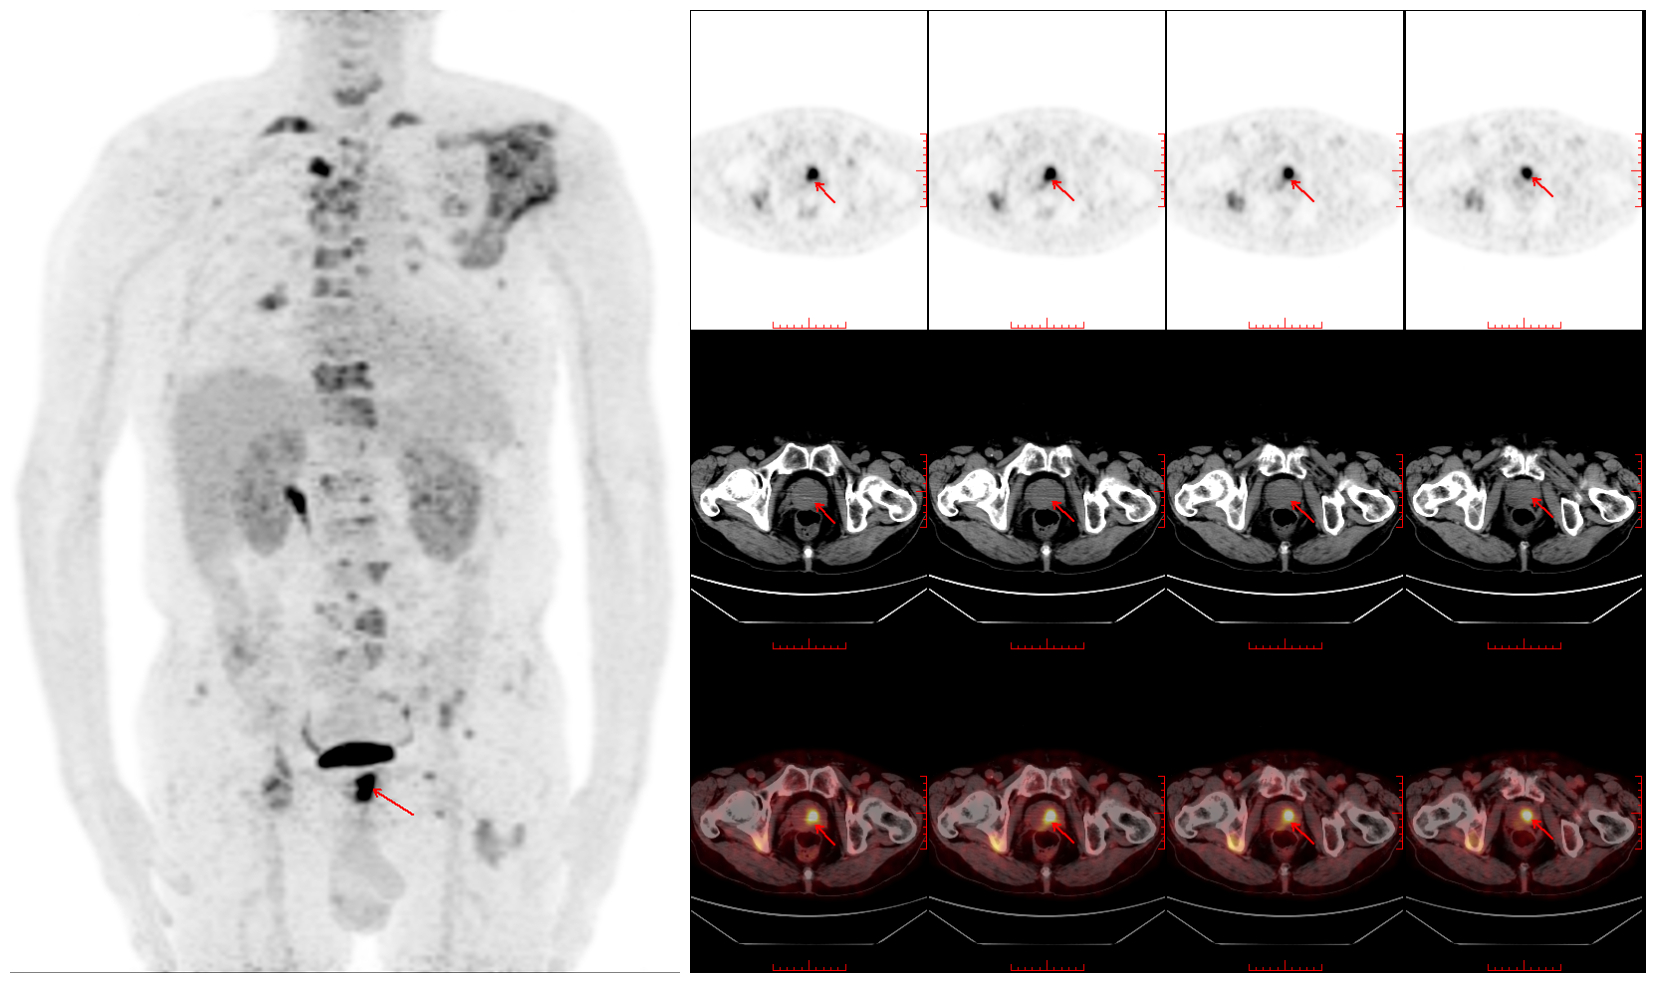

病例一 PET-CT检查寻找原发灶 患者,男,77岁,外院CT示全身多处骨质异常,考虑肿瘤性病变;我院骨显像示:全身多处骨骼骨代谢异常增高灶,考虑肿瘤多发骨转移。行PET-CT寻找原发灶,PET-CT检查示前列腺左叶18F-FDG摄取异常增高,不除外前列腺癌可能。穿刺后病检证实前列腺癌。